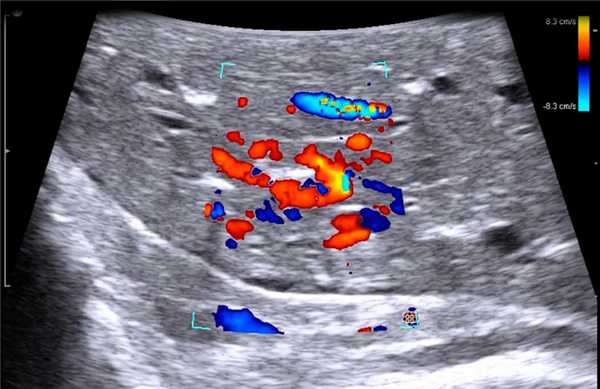

Среди всех интраоперационных исследований основная доля приходится на ИОУЗИ печени. Главная задача - это выявление мелких непальпируемых вторичных образований до 1,0 см, которые трудно диагностируются на дооперационном этапе. Следует обращать внимание на любые изменения структуры и эхогенности паренхимы печени, т.к. картина метастатического поражения полиморфна и разнообразна в зависимости от первичного очага. Наиболее часто небольшие метастазы представляют собой гипо- или изоэхогенные округлые структуры, окруженные гипоэхогенных ободком, аваскулярные в режиме ЦДК. При осмотре крупных очагов оценивают их границы и взаимоотношение с крупными сосудистыми структурами [21]. Оценка границ поражения наиболее актуальна при операциях по поводу алвеококкоза, когда вероятность послеоперационного рецидива обратно пропорциональная радикальности выполненного вмешательства.

Клинический пример N2. Пациентка Р. находилась на лечении в ГУРОНЦ РАМН. При прохождении обследования был установлен диагноз рак толстой кишки. По данным ультразвуковой компьютерной томографии на фоне выраженной диффузной неоднородности паренхимы печени очаговые образования не определялись. При проведении ангиографии и компьютерной томографии так же убедительных данных за наличие метастазов в печень получено не было. При интраоперационном ультразвуковом исследовании были выявлены два очага, характерными особенностями которых являлись малые размеры (0,2 - 0,4 см), а так же нечеткость контуров и изоэхогенность структуры (рис. 1 а,б).

Рис. 1. Метастатические очаги (стрелки) в печени при интраоперационной ультразвуковой томографии.

Особенностью проведения интраоперационного ультразвукового исследования у пациентов с первичным поражением печени является то, что гепатоцеллюлярный рак часто развивается на фоне цирроза печени. Следовательно, если опухоль локализуется в толще паренхимы, а так же имеет не большие размеры, пальпаторно определить ее границы крайне затруднительно. Таким образом, задачи установленные перед интраоперационной ультразвуковой томографией были несколько иными, а именно: определение границ опухоли, разметка зоны резекции, определение связи с магистральными сосудами (рис. 2 а,б).

Рис. 2. Метастатические очаги (стрелки) в печени на фоне цирроза.